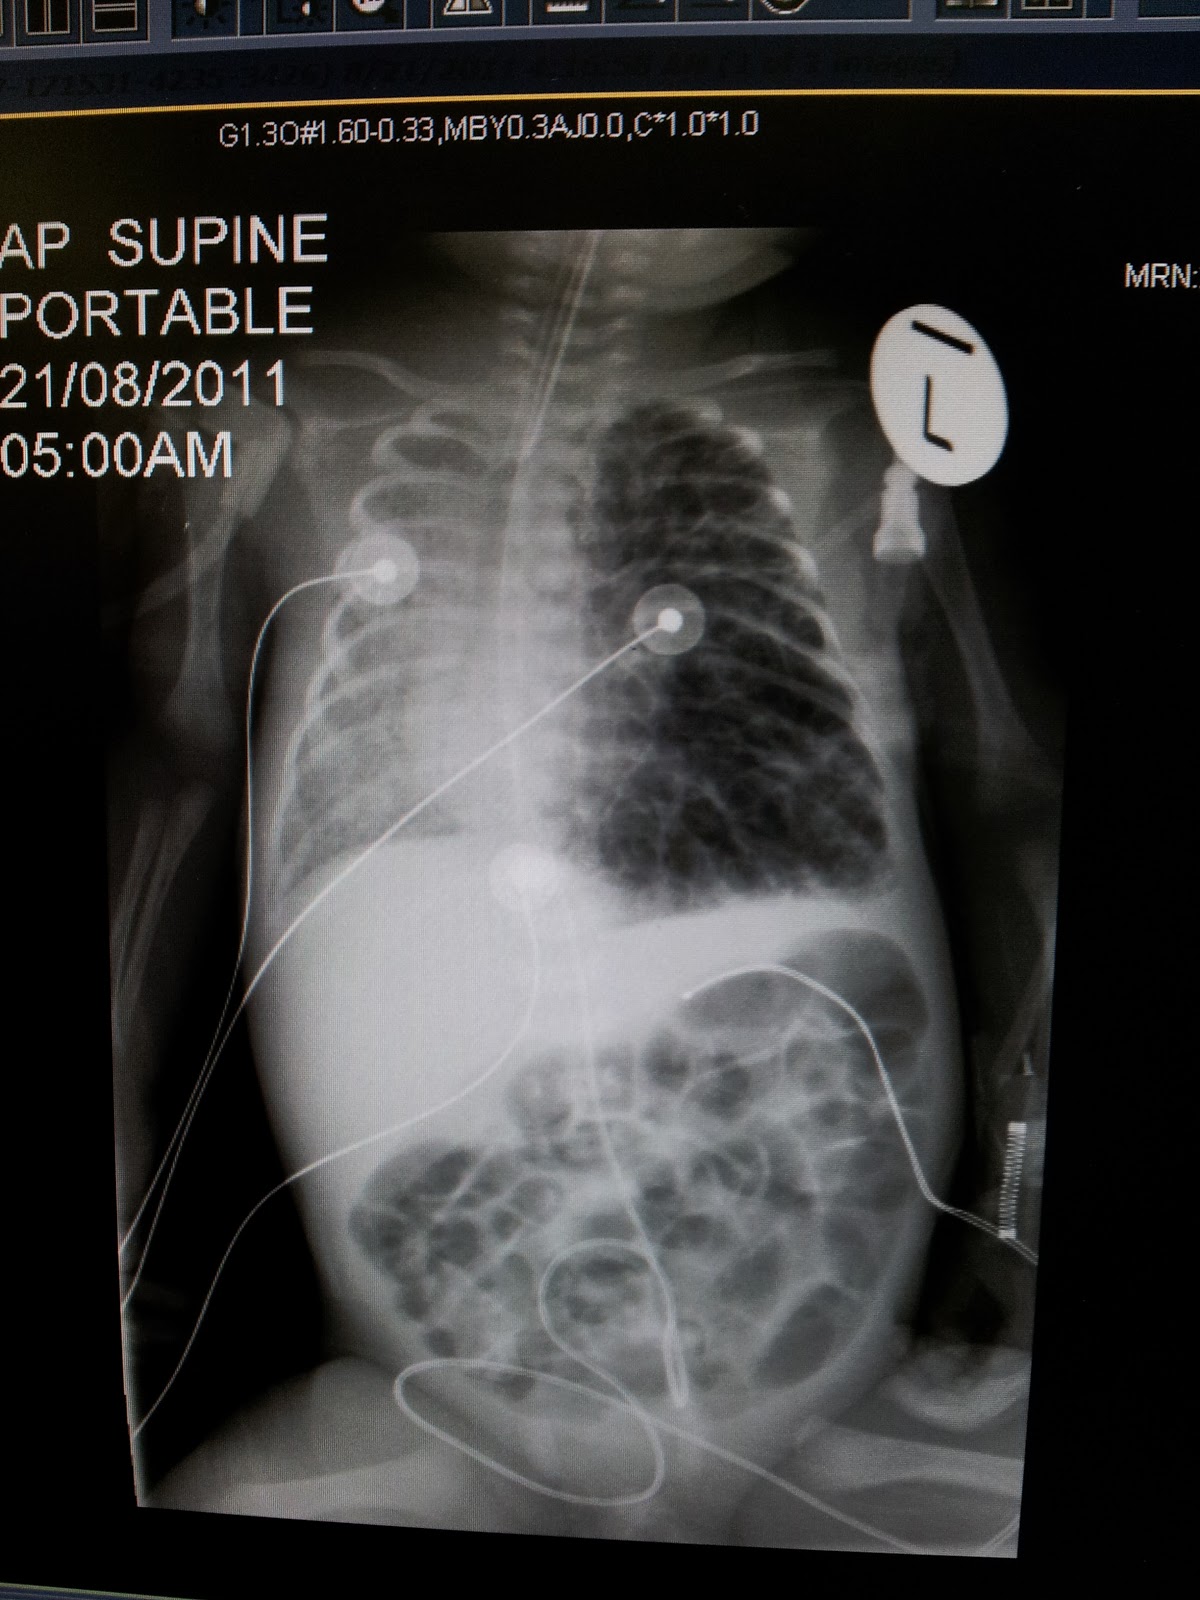

From emj.bmj.com

Air in the lung can you spot them? Emergency Medicine Journal Air Pocket Lung Disease emphysema is a type of chronic obstructive pulmonary disease (copd) that causes damage to the walls of the alveoli. It is a form of chronic. In people with emphysema, the air sacs in the lungs (alveoli) are damaged. emphysema is a lung disease that results from damage to the walls of the alveoli in your lungs. Be occurs. Air Pocket Lung Disease.